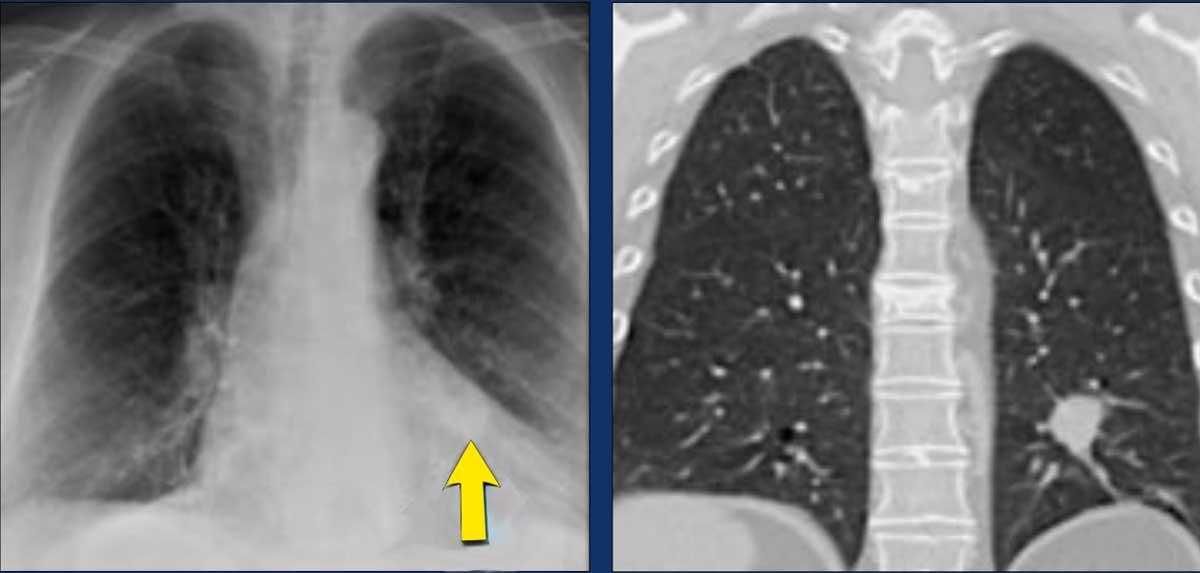

3. Tổn thương kính mờ hoặc dạng lepidic đa ổ

- Giai đoạn T được xác định bởi tổn thương chiếm ưu thế nhất.

- Một phân loại N và M duy nhất được áp dụng cho tất cả các tổn thương.

- Tính đa ổ được ký hiệu là (#/m), ví dụ ba tổn thương được ký hiệu là 3/m.

Ví dụ:

- T1aN0M0 (2/m), với phân loại T1a dựa trên tổn thương chiếm ưu thế ở thùy dưới phổi phải (RLL).